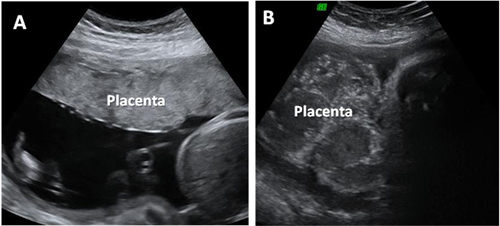

La ecografía 2D nos muestra cómo en una placenta joven, en buen estado, y cómo es una placenta envejecida. En el segundo caso pueden observarse calcificaciones placentarias, lo cual le hace cambiar de textura. Constituye un riesgo para el embarazo al no aportar suficiente oxígeno y nutrientes al bebé.

Ecografía de placentas en el tercer trimestre de embarazo

En la imagen de la izquierda (A), podemos observar una placenta joven; y en la imagen de la derecha (B) visualizamos una placenta envejecida, con una textura diferente y gran cantidad de calcificaciones a la vista.